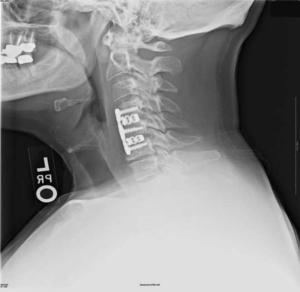

Импланты шейного отдела позвоночника на рентгене.

Если клиника симптомов не поддается консервативной терапии или неинвазивные способы не могут быть задействованными ввиду сильно прогрессирующего стеноза, назначается операция. Вмешательство предполагает использование декомпрессионной ламинэктомии под общим наркозом. При комбинированной проблеме, например, вместе с грыжей, ее сочетают с микродискэктомией и спондилодезом. При спондилодезе осуществляют скрепление смежных позвонков металлическими фиксаторами (стержнями, пластинами, крючками и пр.), установку межтеловых имплантатов или вживление костного трансплантата с металлической гильзой.